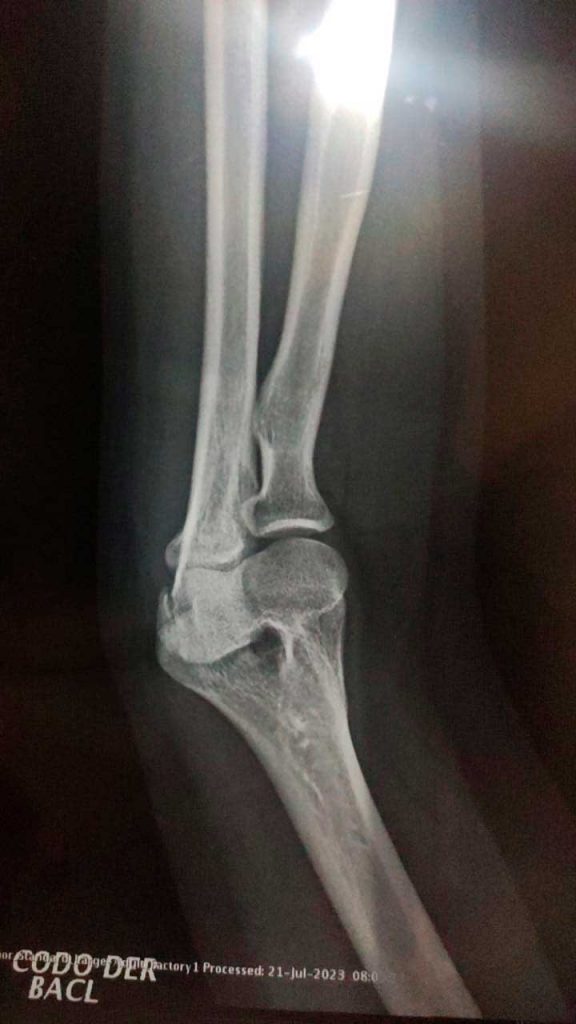

Cuando Ana Ginelly recuperó la conciencia, sólo era capaz de percibir el intenso dolor en su brazo; más tarde se le diagnosticó una fractura de cúbito.

Después de varios trámites, sus padres la trasladaron por su cuenta a una clínica privada donde recibió atención integral: estudios, tomografías y una revisión completa para descartar daños internos.

Aunque pudo salir el mismo día, su recuperación no fue inmediata. La movilidad del brazo se vio reducida durante meses, y aún hoy padece molestias cervicales. Además, desarrolló temor al transitar por calles de la ciudad, especialmente en moto.